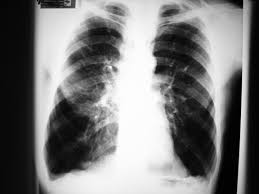

Covid-19: Renova apoia CHMT com a oferta de equipamentos Raio X